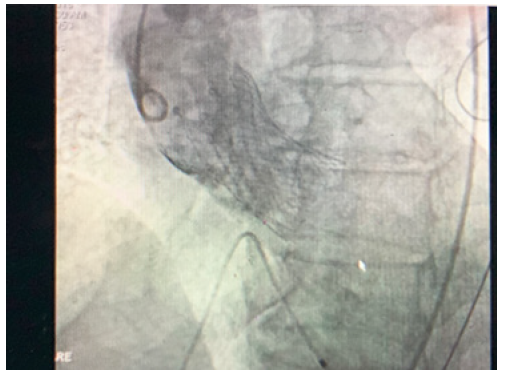

After repeated attempts it was decided to try an alternative approach. The right femoral vein was accessed and an 8F sheath inserted. Transeptal puncture was performed with a Brockenbrough needle and long Terumo wire passed through the left atrium to the left ventricle. The wire could then easily pass retrogradely through the aortic valve down to the descending aorta. The wire was then snared out of femoral artery. A multipurpose catheter was then passed over the wire and antegradely into the left ventricle and the guide wire exchanged. Finally, he nailed the wire to the right sheet of the TAVI. By pulling like this, the wire of the TAVI could cross the calcified valve. The cardiologist after passing the wire through aortic calcified valve put a balloon for the dilatation of the very stenotic valve. This venous-arterial wire loop is used to pass TAVI catheter through aortic valve. After the dilatation of the stenotic aortic valve with the balloon, the procedure continues as standard transfemoral approach. Medtronic Evolut valve was implanted successfully (Figure 1)(Figure 2)(Figure 3).

So direct implantation of Revolute R valve has been done, and the valve was perfectly in place. No need of post dilatation. It is a Medtronic Core Valve Evolut 34mm. The vascular femoral sheet is a proglide 6F (2mm). No major aortic regurgitation after the valve was in place and patient was in sinus rhythm. Temporary pacemaker fixed (Figure 4).